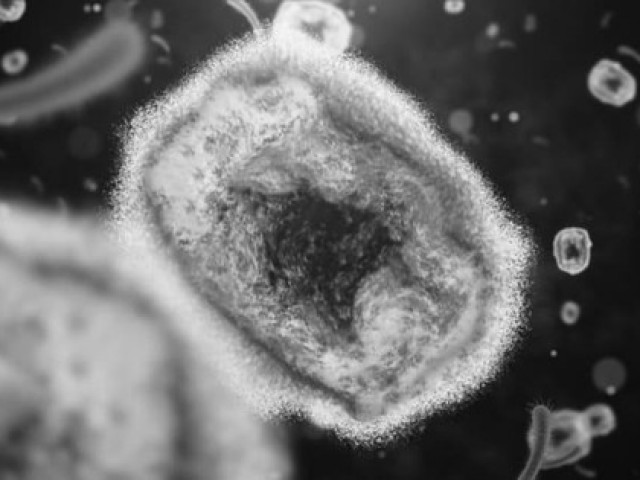

TS.BS Nguyễn Đăng Mạnh, Viện trưởng Viện Lâm sàng các bệnh truyền nhiễm cho biết, bệnh thủy đậu do virus Varicella Zoster gây ra. Virus Varicella Zoster gây bệnh thủy đậu chủ yếu lây truyền qua đường hô hấp, bằng các giọt nước nhỏ trong không khí bắn ra từ đường hô hấp như mũi, miệng của người bệnh, thông qua việc tiếp xúc trực tiếp với đồ vật như quần áo, chăn gối có vấy bẩn các chất tiết của người bệnh, qua tiếp xúc trực tiếp với chất dịch khi các bọng nước bị vỡ.